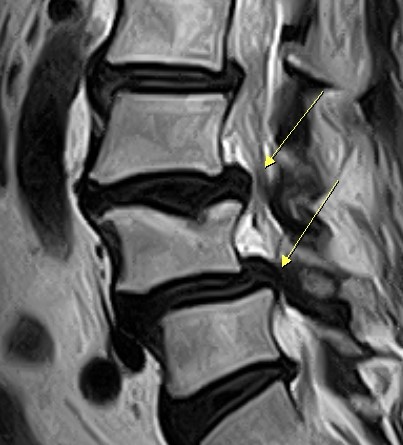

活力得中山脊椎外科醫院院長楊椒喬指出,患者約5年前出現下背及雙大腿皆有痠痛情形,曾去推拿、針灸,但效果都不明顯;最近幾個月痠痛情形加重,無法久走,右腳趾感到麻刺情形。經安排核磁共振檢查,發現患者腰椎第3至4至5節椎間盤突出且合併滑脫。

考量患者症狀,楊椒喬建議她接受腰椎融合手術,同時,分別在腰椎第3至第4及第4至第5節置入新式撐開式支架。撐開式支架本身體積小,於未撐開前高度及寬度均僅不到1公分,能避免植入時對肌肉及神經等組織摩擦,降低術後疼痛感。放入椎間後,再撐開調整高度,並有多種支架高度可做搭配,適應人體結構,有利於不同病人使用,恢復到理想的椎間高度,達到最好的手術效果。